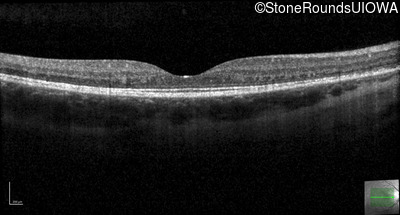

Optical Coherence Tomography - Left - 20/50

Exemplar / OCT Stack

OCT Stack